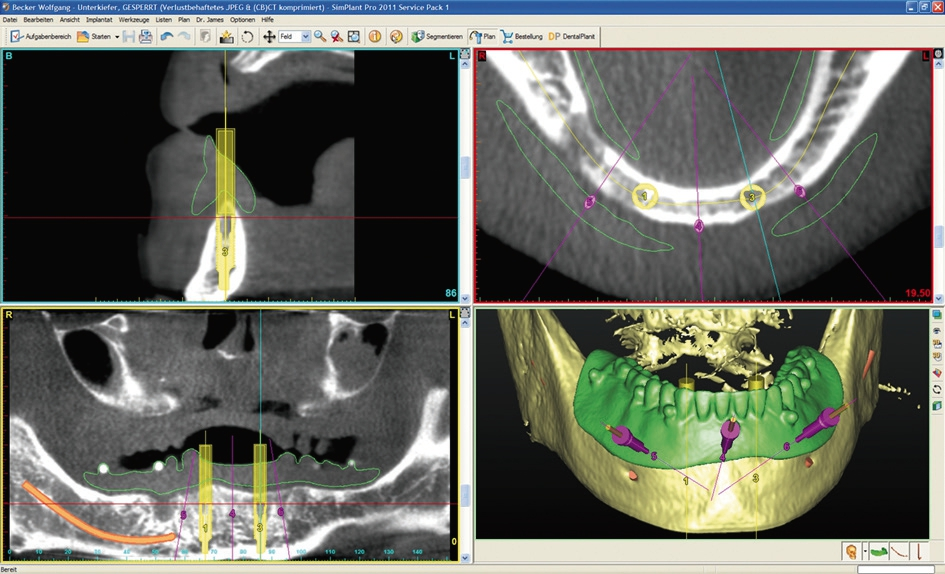

Abb. 3: Die Planung der Position der Implantate und der Befestigungpins für die SOS-Schablone erfolgt anhand einer DVT-Aufnahme, z. B. im SimPlant oder Magellan Programm.